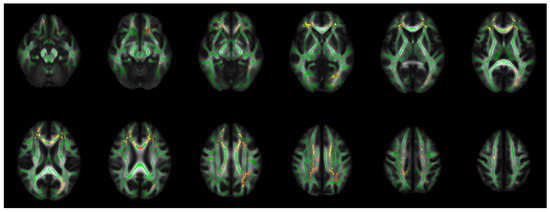

| PBD Compared to HC | |

|---|---|

| Findings | WM Tracts |

| Decreased FA (ptfce-FWE < 0.012 *) | Left parietal and occipital WM |

| Increased MD (ptfce-FWE < 0.012 *) | Left Fmin, gCC, bCC, ACR, SCR, and inferior frontal WM |

| Increased RD (ptfce-FWE < 0.008 **) | Bilateral orbitofrontal cortex WM, Fmin, gCC, bCC, ACR, SCR, PCR, anterior cingulum, inferior frontal WM, bottom part of the superior parietal lobule WM, posterior part of the superior longitudinal fasciculus, and posterior cingulum The left posterior part of the inferior fronto-occipital fasciculus and ILF, posterior thalamic radiation, optic radiation, lingual gyrus WM, splenium of the CC, forceps major, and the temporal part of the IFL |

| PBD Compared to NPBD | |

| Decreased FA (ptfce-FWE < 0.014 *) | Left parietal and occipital WM |

| Increased RD (ptfce-FWE < 0.014 *) | Left Fmin, gCC, bCC, and ACR |